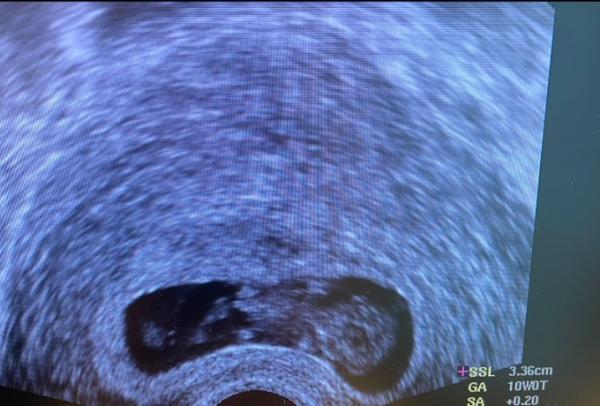

Hallo ihr lieben, Heute hatte ich meinen Termin beim FA und bin mega glücklich, weil ich so Angst hatte vor einer weiteren Fehlgeburt und weil ich mich seit der 9 Woche total unschwanger gefühlt hab. das Baby ist zeitgerecht, hat sich bewegt und ich bin happy

Bild zu Überglücklich vom Ultraschall zurück - Forum für Juni - Mamis

Woow wie toll das Bild! Herzlichen Glückwunsch